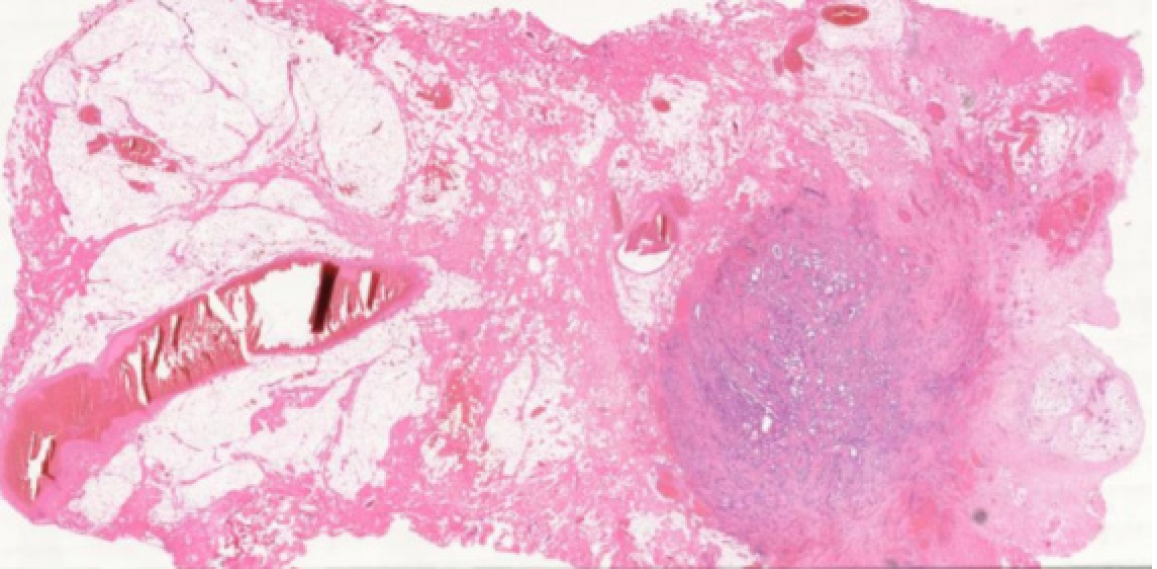

Figure 2 Histopathology specimen of papillary thyroid carcinoma of the pyramidal lobe.